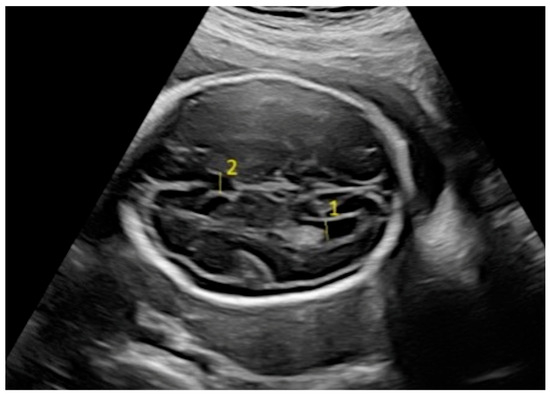

Fetal biometric parameters and fetal intracranial structures were assessed via ultrasonography. The following fetal intracranial measurements were included: posterior lateral ventricle (PLV), cavum septi pellucidum (CSP), thalamus, cisterna magna (CM), and transverse cerebellar diameter (TCD). Prenatal ultrasonographic examinations were performed using a Voluson E8 Expert system (GE Healthcare, Tiefenbach, Austria) equipped with a 2–9 MHz 2D curvilinear transducer. All ultrasound assessments were conducted once by the same perinatologist, following the guidelines of the International Society of Ultrasound in Obstetrics and Gynecology and the World Association of Perinatal Medicine [18,19]. The PLV was measured on an axial transventricular plane that displays the anterior and posterior horns of the lateral ventricles, at the level of the atrium, perpendicular to the long axis of the ventricle. Calipers were placed on the inner (echogenic) edges of the ventricle walls at the widest point (inner-to-inner measurement). The thalamus, cerebellum, and CM were visualized on a transcerebellar plane. The transverse thalamic diameter was measured between the widest points of the thalami. For the TCD, calipers were placed on the outer edges of the cerebellum. CM was measured as the greatest distance between the posterior edge of the cerebellar vermis and the inner surface of the occipital bone. CSP was assessed on both the transventricular and transcerebellar planes, with the measurement taken on the transventricular plane. CSP width was measured from inner edge to inner edge, perpendicular to the midline (Figure 1 and Figure 2).

Figure 2. Fetal intracranial structures in the transventricular plane (1: posterior lateral ventricle; 2: cavum septum pellucidum).